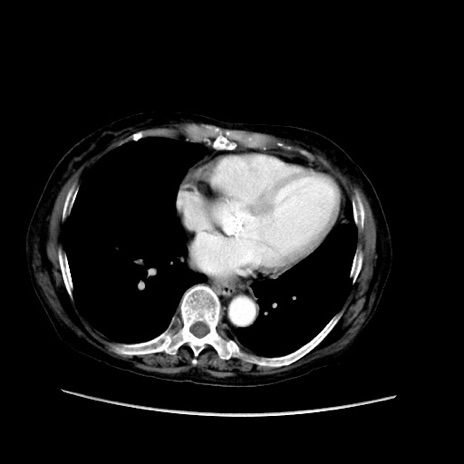

症例31(横断像)

【症例】80歳代 女性

【主訴】腹部膨満感

【現病歴】他院にて肝硬変にてフォロー中。1週間前から便秘、腹部膨満感、臍部腫瘤あり受診となる。

【既往歴】肝硬変

【身体所見】腹部膨隆あり、皮膚変化なし、疼痛なし。

【データ】WBC 4600、CRP 0.25